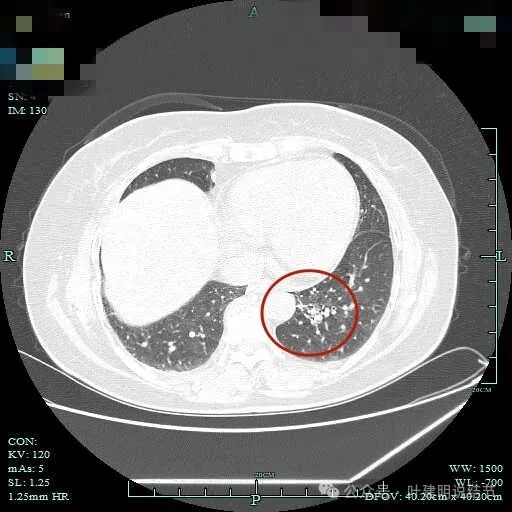

病灶轮廓欠清,较为散在,缺乏聚拢性,似乎有些像斑点状。

有少许磨玻璃成分出现,较前面层面整体轮廓显得清楚点。

到这层面,聚拢性较前明显,密度显杂乱。

磨玻璃成分更明显,实性成分也明显,实性部分收缩力不强,表面不平整,感觉边缘毛糙。

表面浅分叶,磨玻璃成分明显,实性部分密度较高。

表面不平,磨玻璃部分的轮廓与边界清,实性部分占比不小,缺乏收缩力,像是腺泡型。

实性成分占比较高,边上有明显磨玻璃成分,说明含贴亚型。

灶内有小空泡征,磨玻璃部分轮廓与边界清,实性部分虽明显但毛刺征或收缩力等均不明显。

磨玻璃成分以及灶内空泡征。

灶内细支气管扩张明显,实性成分缺乏收缩力,考虑腺泡亚型。

磨玻璃成分也很明显,考虑含贴壁亚型。

上图大部分是磨玻璃成分,边缘的毛刺征,表面有浅分叶。

上图层面已经基本上磨玻璃密度,轮廓清,灶内有囊腔样灶,表面不平。

边缘略显糊,与膈肌贴着。

远侧端有阻塞性炎症的表现,病灶在些层也是磨玻璃密度。

边缘区域略显轮廓不清。